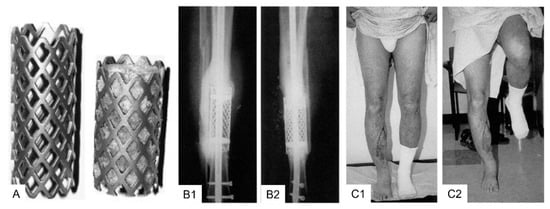

3.2. Clinical Application Cylindrical (Spinal) Titanium Mesh Cages for Long Bone Defects

The first clinical application of cylindrical (spinal) titanium mesh cages (DePuy Motech, Warsaw, IN, USA) was described in 1999 for combination with cancellous bone allograft and demineralized bone matrix for the reconstruction of posttraumatic diaphyseal tibial defects in two patients [123]. The mesh cages were cut to a length circa one cm longer than the defect and reinforced at both ends with internal rings attached to the cage. The authors reported that both patients reconstructed with the spinal titanium mesh cage were able to begin unrestricted weight-bearing early and achieved complete functional recovery with restored limb alignment [123]. Moreover, bony consolidation of the defect was confirmed one year postoperatively by plain radiography and computed tomography (CT) imaging, which confirmed bone healing circumferentially within the mesh and at the interfaces between the host bone and the cage [123]. Thus, this new single-stage reconstruction method using cylindrical modified spine titanium mesh cages loaded with allograft in combination with internal or external fixation immediately restored bone continuity, alignment, and stability (Figure 4).